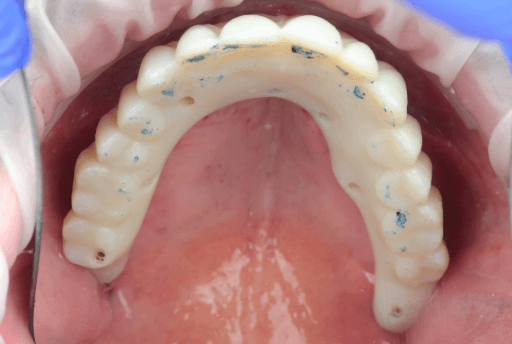

3.6 Clinical Delivery of the Temporary Full-Arch Implant-Supported Appliances

The temporary MUA screw-retained prosthesis were installed in the patient's mouth and occlusion was checked. From the clinical perspective, occlusal contacts required minimal correction as the occlusion was already accurately planned in the CAD software. The patient expressed comfort and reported to be satisfied with the esthetic outcome.

A carefully controlled occlusal scheme with reduced posterior contacts was adopted to minimize overload during osseointegration. The patient was instructed to follow a soft diet during the initial healing phase.

Occlusion check of upper All-on-X appliance

Occlusion check of lower All-on-X appliance

Occlusion check of All-on-X appliance

Upper, lower, and occlusion check of the temporary full-arch implant-supported appliances.